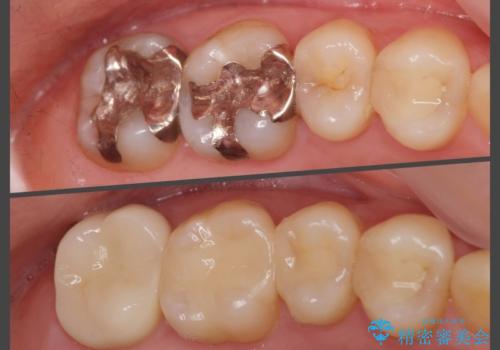

クラウン下に再発した虫歯 審美ブリッジによる補綴

X線写真を撮影するとクラウン・コアの下に黒い影が認められます。これは内部に虫歯が再発した可能性が示唆され、深い虫歯となり抜歯を余儀なくされる可能性があります。

クラウン・コアを顕微鏡下で慎重に外したところ、やはり大きな虫歯が存在し、取り切ると今後歯を維持することが難しい状況であったため、抜歯を行い大規模な手術が必要のないブリッジで審美性の回復を行うことになりました。

前回行われた治療では虫歯を取り残していたか、コア・クラウンの治療・製作の精度が低かったために内部に大きな虫歯が再発してしまったと考えられます。

当グループでは虫歯やクラウンの製作過程で必ず拡大鏡・顕微鏡を用い、精密な治療を心がけることで虫歯の再発リスクを極力排しております。